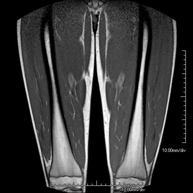

Exploración ideal para el estudio de lesiones en músculos isquiotibiales y cuadriceps, frecuentemente lesionados en deportistas. También permite una buena valoración de tendones y nervios periféricos. Tiene una duración aproximada de 20 minutos. No emplea radiación ionizante. - RM Rodilla

Exploración para el estudio de lesiones en tendones, músculos y nervios periféricos. De gran utilidad para el diagnóstico de las roturas fibrilares en gemelos. Tiene una duración aproximada de 18 minutos. No emplea radiación ionizante. - RM Tobillo